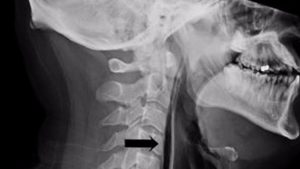

وفي البداية، رأى الأطباء أن الرجل أُصيب بتورم في عنقه، وعندما قاموا بفحص الأنسجة الرخوة، أصدرت صوت فرقعة. وأوضحت يانغ أن هذا يعني أن هناك فقاعات من الهواء دخلت في عضلات الرجل إلى عمق أنسجته.

وأكد المسح الضوئي المشكلة، وأظهرت الاختبارات الشرائط الفعلية من الهواء في المنطقة خلف البلعوم وفي الرقبة الأمامية وصولاً إلى القصبة الهوائية. وبعبارة أخرى، فإنه من خلال محاولة كتم عطسته، تسبب الرجل بثقب صغير في حلقه.